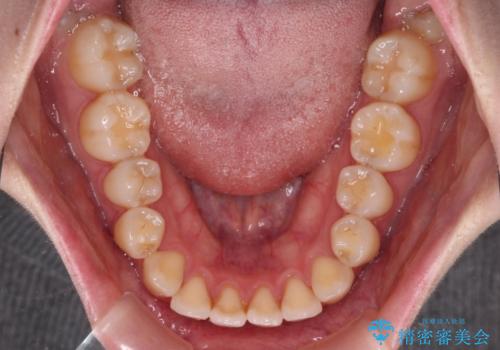

- 上下前歯の隙間を気にして来院された患者様です。

前歯が、舌の突出癖により上下前歯が非接触となっている状態でした。

ワイヤー矯正での開咬改善には時間がかかります。

舌の突出癖改善のトレーニングをしっかりと行っていただき、上下前歯が接触する咬み合わせを達成することができました。